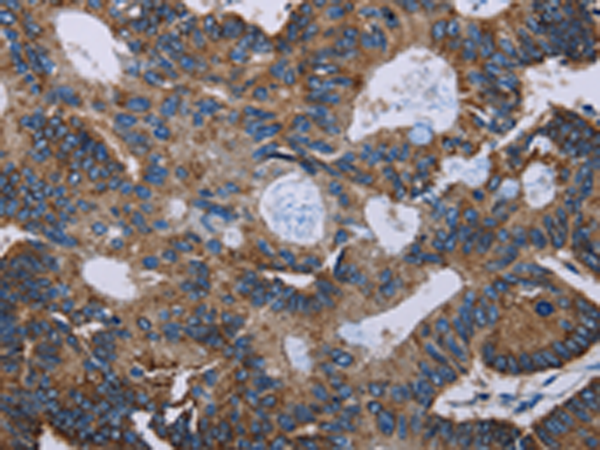

分类: 科研抗体货号: P08471别名: PHA; LMN2R; TDRD18; DHCR14B应用: WB,IHC反应种属: Human

分类: 科研抗体货号: P08481别名:应用: IHC反应种属: Human, Mouse